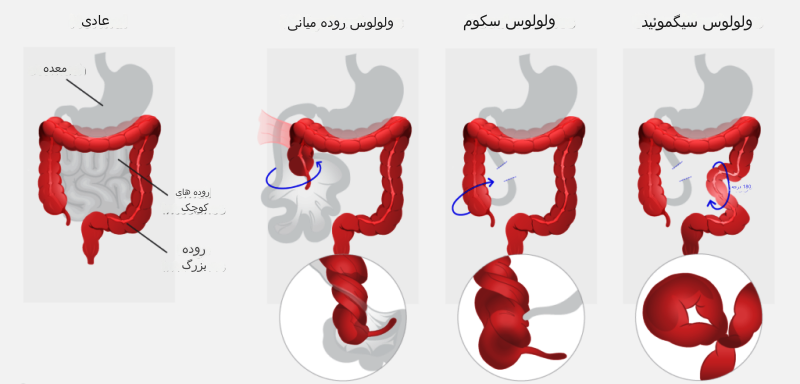

- ولولوس یا پیچ خوردن روده: این عارضه منجر به انسداد جزئی یا کامل روده شده و مانع حرکت مدفوع در روده خواهد شد.